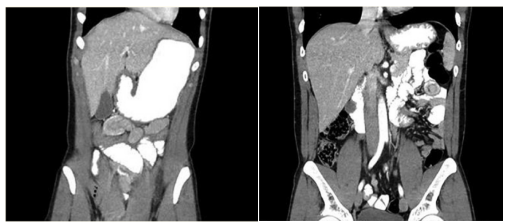

回顾性分析了2016-2018年两家教学医院11例急性腹痛患者,均为使用大麻后引起的肠套叠,患者年龄范围18-38岁,多数患者表现为弥漫性腹痛,一半以上患者表现为肠梗阻症状,行腹部CT检查,均报告空肠肠套叠,如图1.2所示。两名患者行诊断性腹腔镜探查,一名患者行腹腔镜手术,其余患者行保守治疗,患者住院时间中位数2天,腹腔镜干预的患者住院平均时间2.5天,保守治疗的患者住院平均时间2.4天,具体患者人口统计学,临床表现及治疗过程如表1。

图1 一名24岁女性,腹部CT提示梗阻部位位于中腹部,肠套叠

图2 一名30岁男性 腹部CT提示梗阻位于左上腹,肠套叠